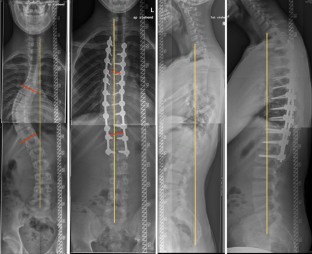

Abb. 3

Ziel der vorliegenden Studie ist es, den Effekt verschiedener dorsaler Operationstechniken auf das sagittale Profil zu untersuchen. Retrospektiv wurden 36 Patienten mit thorakaler idiopathischen Adoleszentenskoliose eingeschlossen, welche mittels dorsaler Korrekturspondylodese versorgt wurden. Unter Berücksichtigung verschiedener Korrekturprinzipien wurden die Patienten in Subgruppen eingeteilt (A Pedikelschraube, B Langkopfpedikelschraube, C Langkopfpedikelschraube mit Ponte-Osteotomien). Standardröntgenaufnahmen der ganzen Wirbelsäule im Stehen wurden vor und mindestens 2 Jahre nach dorsaler Korrektur angefertigt. Eine Subgruppenanalyse wurde zur Detektierung von Gruppenunterschieden vorgenommen.

The purpose of this study was to evaluate the effects of different posterior correction techniques on sagittal profile and balance. A total of 36 consecutive patients with thoracic AIS, who were treated with selective thoracic posterior correction were included in this retrospective study. The patients were further assigned to three different subgroups according to different surgical strategies: A: pedicle screws, B: long-head pedicle screws and C: additional Ponte osteotomy. Standardized radiographs in the standing position of the whole spine in two planes were evaluated before and at least 2 years after correction for all patients and a subgroup analysis was done to identify differences between the three groups.

A significant correction of the major curve was achieved in all three groups (p < 0.001). There was a significant difference between the groups with groups B and C showing significantly higher levels of major curve correction in comparison to group A (p < 0.001). Concerning the sagittal profile, there was a significant difference in the development of thoracic kyphosis (TK) and lumbar lordosis (LL). While a significant reduction of TK and LL was found in groups A and B after surgery, a significant increase of TK and LL was noted in group C which was associated with a decrease of pelvic tilt and an increase of sacral slope. The 2-year follow-up showed the lowest ODI-% value only in group C which was positively correlated with reduction in pelvic tilt.